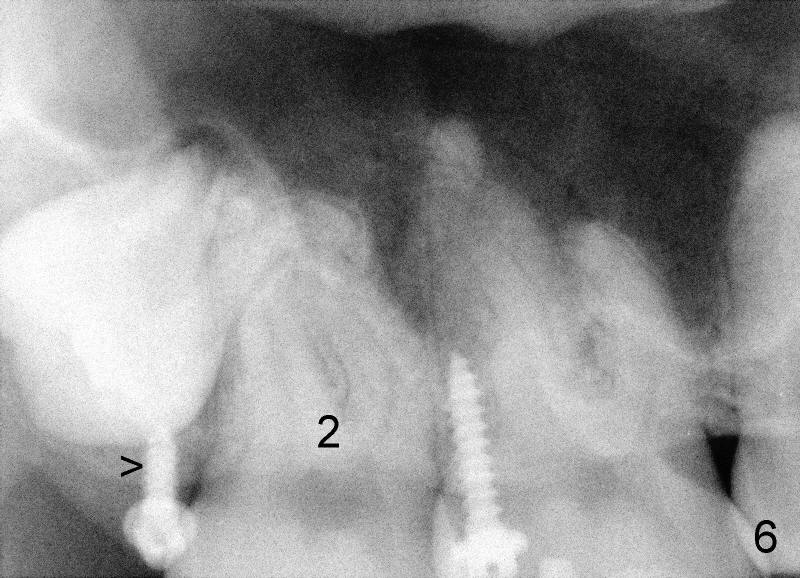

Eight mm of Ancor mini-implant is placed on the mesiobuccal of #2, whereas 6 mm on distopalatal (Fig.3,6 <) without sign of hemorrhage. But a few days later, the patient's father calls, saying that one of mini is out (palatal). The palatal mucoperiosteum is thicker than buccal. Longer mini-implant should have been used (8 or 10 mm). The excuse for short mini in the palate is that there is not much soft tissue (presumably hard tissue) distal to #2. In fact, the patient is dental phobic. Who will faint first dealing with the fearful patient for the same procedure for a second time?

Mini penetration does create soft tissue shaving, which may cause epithelial entrapment and therefore potential mini loosening. At time of placement, it is a minor issue, in comparison to violation of root surface. As the mini goes down, torque builds up. Finally the handpiece halts. Then use a wrench to slowly rotate the mini down while watching for patient's reaction. It appears that the mini eventually has resistance (touching root surface?). The mini does not seat completely (Fig.4 >, as compared to Fig.3 <), but it is solid. When power chain is loaded, it is apparent that the patient feels more pressure upon #2. The patient tolerates the procedure with topical well. It feels like that champagne is needed for celebration. Sweeter is taking and looking at immediately post-op PA (Fig.7 >).

The tooth #31 is uprighted in six months (Fig.8, as compared to Fig.5). The edentulous space increases from 6 mm to 9 mm mesiodistally, which is still not enough. The M-D width of #19 is 12 mm. In fact, the tooth #2 has been intruded substantially (Fig.9. Compare to Fig.3). The possible reason for resistance of distal movement of #31 is an interference from the tooth #3 (Fig.10). A regular implant is placed intentionally in the distal aspect of the edentulous area (Fig.11: I). The next plan is to place temporary crown on the implant once it osteointegrates to raise the occlusion efficiently so that the tooth #31 is free to move distally with retraction of power chain attached to the mini-implant (as shown in Fig.2). The regular implant may be also used as anchorage to push #31 distally. See you later.